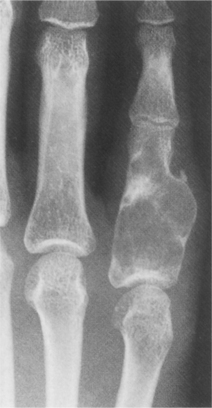

Pathologic examination of the neoplasm reveals a tumor that is soft, friable (easily breaks apart), fleshy, and red-brown with yellow areas. The tumor usually extends to but not into the articular cartilage. Destruction of the bone cortex with expansion into soft tissue can occur (Fig. 26-16). Hemorrhage, cyst formation, and necrosis can be seen on gross pathology. Hemorrhage and necrosis (often accompanied by pathologic fracture) occur often in the weight-bearing bones. The tumors can be locally invasive (into bone and soft tissue) with extensive bone destruction and cortical expansion.

Figure 26-16 Giant cell tumor. Gross morphologic features of giant cell tumor. A, Bisected distal end of radius with well-demarcated tumor mass expanding bone contour. Tumor tissue is red-brown with yellow septations. B, Radiographic presentation of tumor showing focal destruction of cortex. (From Dorfman HD, Czerniak B: Bone tumors, St Louis, 1998, Mosby.)